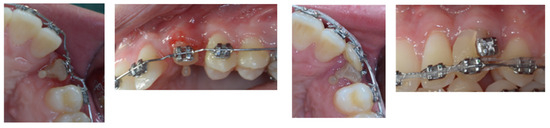

3. Therapeutic Interventions

4. Follow-Up and Outcomes